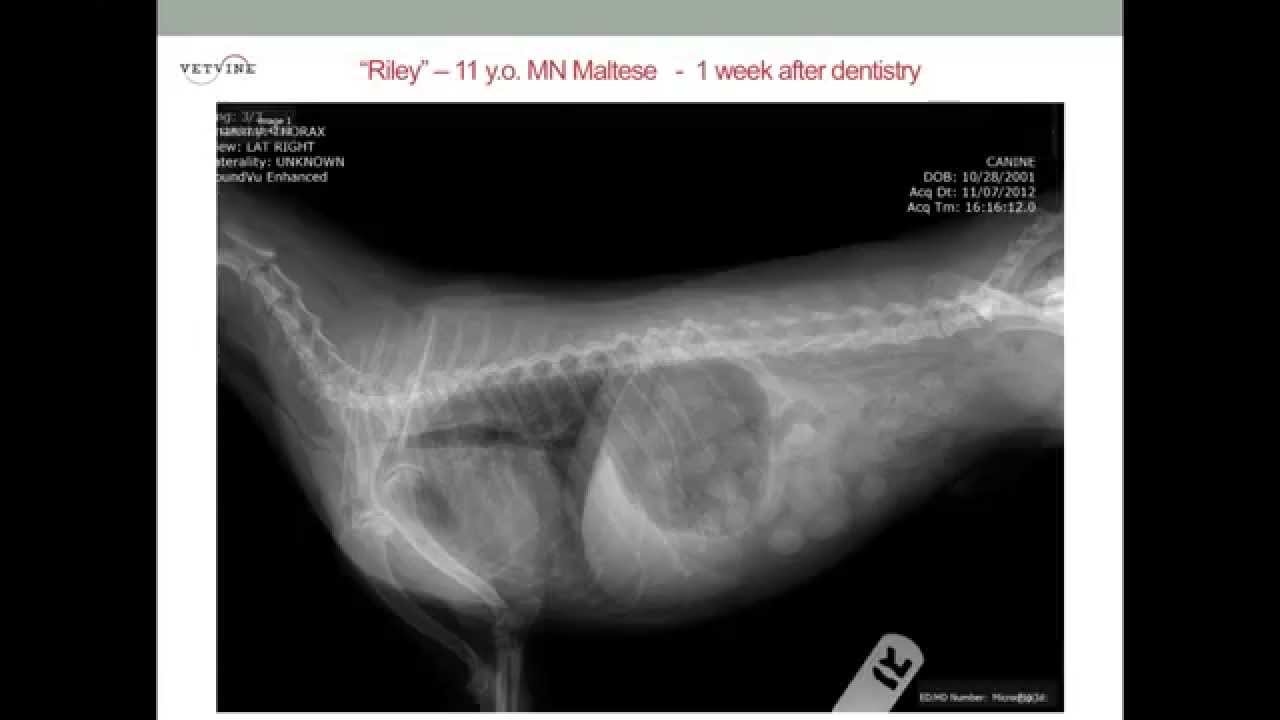

Figure 4 from Radiographic and computed tomographic appearance of tracheal collapse with axial Tracheal Collapse Yorkie Sound Often described as a “honking”. It occurs due to the weakening, or defect, of the tracheal. In this vetgirl vlog, check out the classic sound of a dog with tracheal collapse. Symptoms of tracheal collapse in yorkies can include a persistent cough, fast breathing, gagging, and wheezing. In fact, you can treat this progressive condition with medication and lifestyle changes.. Tracheal Collapse Yorkie Sound.